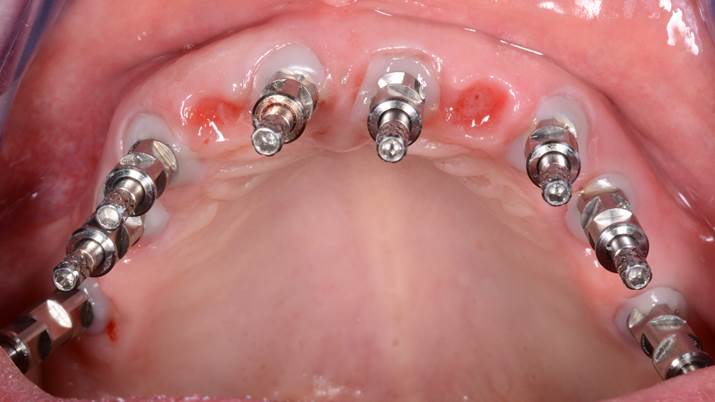

Clinical case: Advantage of fuse abutment with AnyRidge implant for immediate loading in

upper fully edentulous case

- Courtesy of Dr. Kwang Bum Park -

“AnyRidge shows excellent esthetic results

with Zirconia prosthesis in full-mouth rehabilitation case . ”